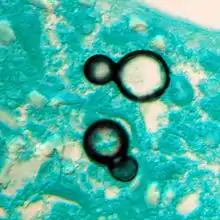

Granuloma with early suppuration. Fungal organisms difficult to recognize at this low magnification.

Large yeast-like fungi seen within giant cells at arrows.

Large yeast-like fungi seen within giant cells at arrows.Budding yeasts in cytoplasm of giant cells at arrows. Broad-based budding and double contoured cell wall seen in the giant cell in the center is characteristic of Blastomyces dermatitidis.